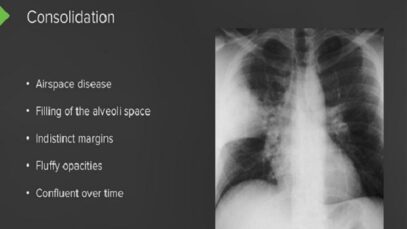

computed tomography of the chest Computed tomography (CT) is an imaging technique that has revolutionized medical imaging. It is widely available, fast, and provides a detailed view of the internal organs and structures. Helical CT is most common, but conventional, axial, step-and-shoot CT is used for thin section high-resolution CT scanning of the lungs, coronary […]